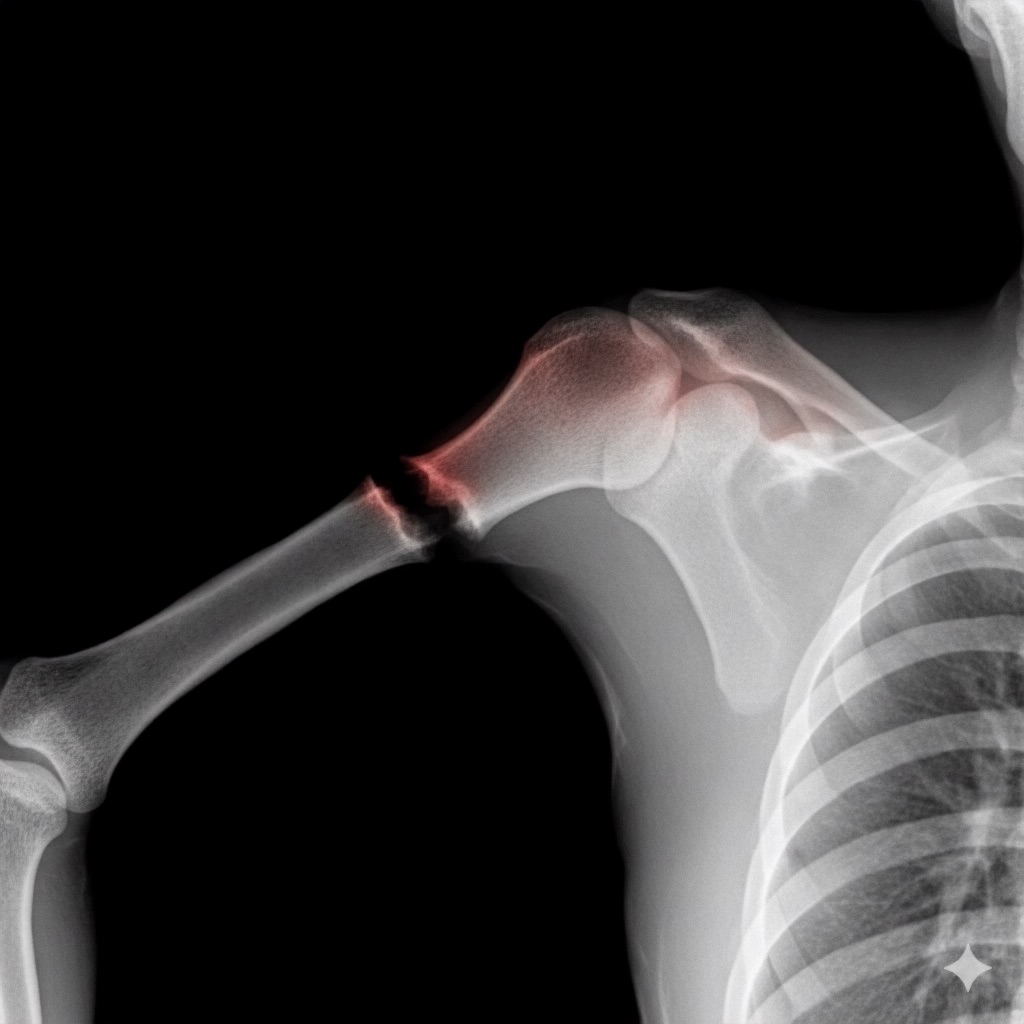

アートや写真の編集用に設計されたFlux Kontextのようなモデルを、医療画像、たとえば「単純な」骨折の赤色マーキングに使用できるか?

即答:面白い結果を出すが、過剰に反応し、医療ツールとしては信頼性に欠ける。これはアイデアを試すためのプロトタイプに過ぎない。

テスト結果:

- 偽陽性 ≈ 24%

- 骨折検出 ≈ 20%

感度モード(検出を優先、ノイズ多め)

- Euler、15ステップ、Karras

- Denoise:1.0

結果:

- 偽陽性 ≈ 80%

- 骨折検出 ≈ 86%